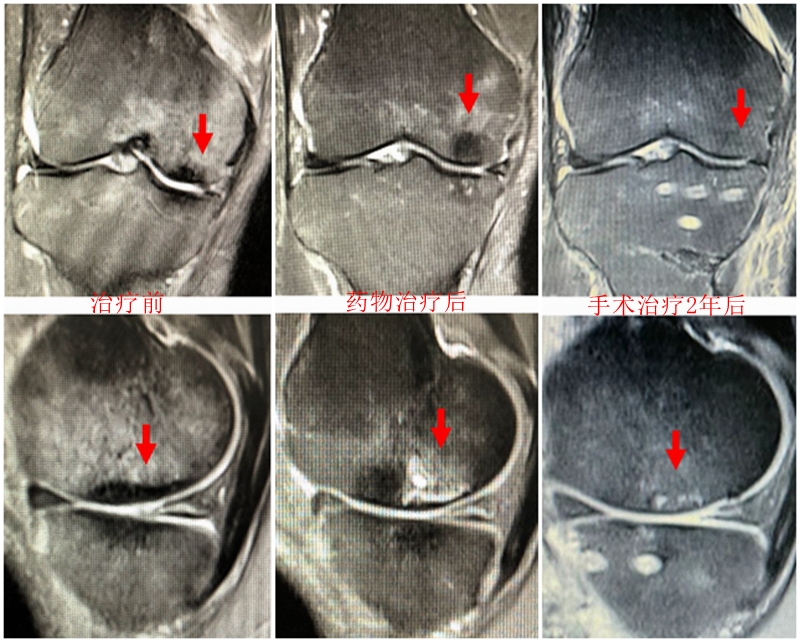

(1)Koshino Ⅰ期 SONK

建议保守治疗,具体方案包括选择消炎止痛药物、抗骨质疏松药物(钙剂、骨化三醇、唑来膦酸钠注射液/地舒单抗注射液)、避免负重及支架保护等方法。

病例:女,65岁,主诉左膝关节内侧疼痛2月余。2017年11月X光未见左膝骨质异常。MR见股骨内侧髁骨坏死,半月板相对突出百分比(RPE)28.3%,合并内侧半月板后根部撕裂,矢状位病变区域前后径为11.67mm,关节线会聚角2.68°

予消炎止痛药物口服、静滴唑来膦酸钠注射液,避免负重6周,后改部分负重,12周后全负重。

2018年2月复查MR见骨髓水肿明显吸收,坏死灶边界清晰,半月板相对突出百分比(RPE)28.92%

2018年6月复查MR见骨髓水肿基本完全吸收,坏死区修复良好,半月板相对突出百分比(RPE)38.54%,患者临床症状消失。

提示坏死好转了,但半月板突出进展了,膝关节的退变加重了。

(2)Koshino Ⅱ期 SONK

优先选择保守治疗方案,或在保守治疗方案的基础上配合行钻孔减压术,由于Koshino Ⅱ期的关节软骨仍相对完整,借助间充质细胞的重建作用及钻孔后骨内压力的降低,在该期仍可取得满意的疗效。

如果保守治疗3个月后症状没有减轻或MR上没有改善时,患者同时存在5个因素中的任一个,则应考虑行手术治疗,选择膝关节镜+自体骨软骨移植术(当患者下肢力线内翻<3°时)、膝关节镜+HTO术、或膝关节镜+HTO+坏死区病灶刮除+自体植骨术。

病例1:女,65岁,主诉右膝关节内侧疼痛1周。2018年1月X光未见右膝骨质异常,MR检查见股骨内侧髁骨坏死,半月板相对突出百分比(RPE)28.99%,关节线会聚角1.4°。

予切开行克氏针钻孔减压,口服消炎止痛药物、钙剂及骨化三醇,不负重6周,后改部分负重至3个月。2018年4月复查MR见骨髓水肿基本完全吸收,坏死区局限并修复良好,半月板相对突出百分比(RPE)32.08%,患者临床症状消失。